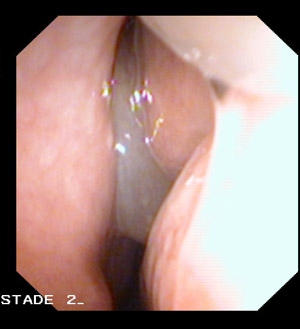

Le diagnostic repose sur l’examen endoscopique des fosses nasales, effectuée par l’ORL. Il met en évidence des polypes multiples de taille variable, translucides, souvent organisés en grappes de raisin.

Polypose endoscopique :

Stade 2 :